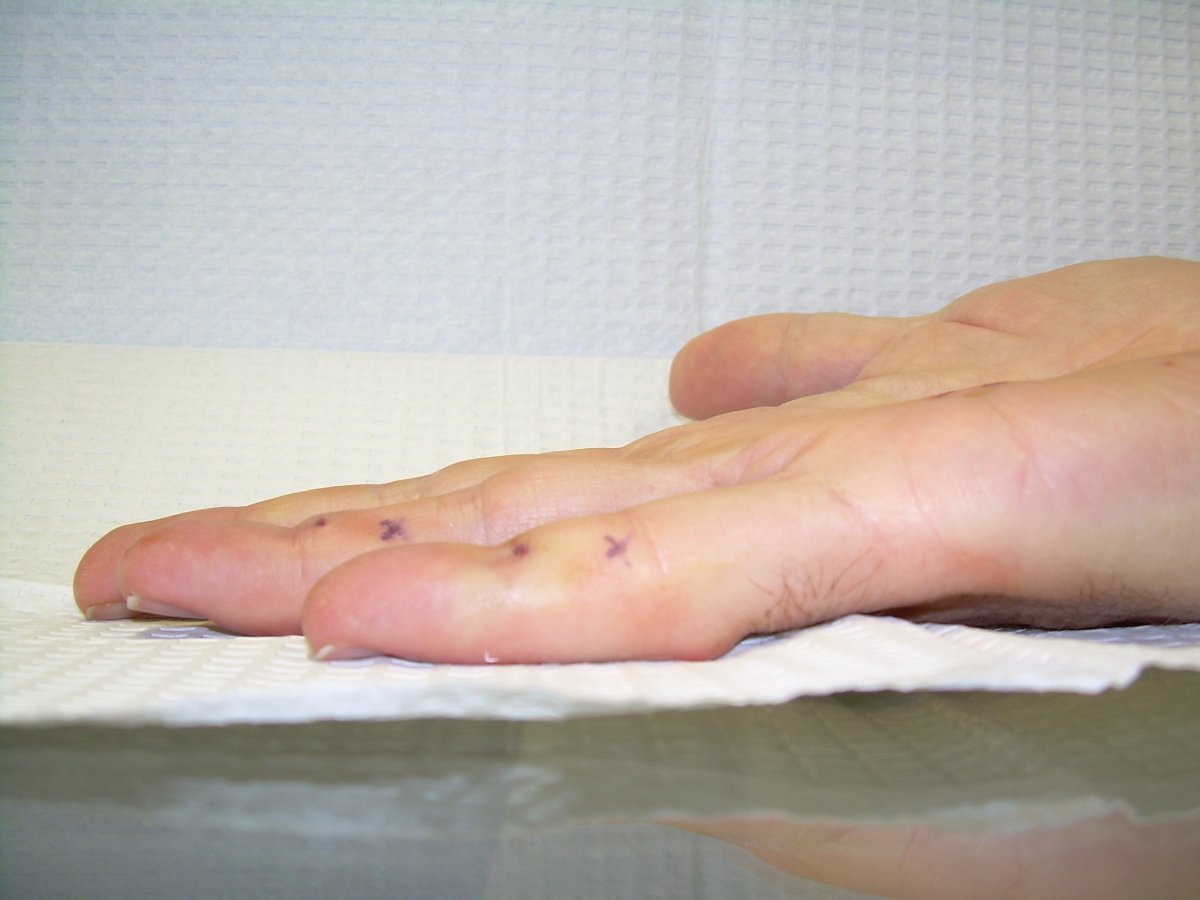

Case 4.

57 year old right handed man with a 22 year

history of Dupuytren disease affecting his

left small finger.

Highslide Highslide

Planning of portals (dots) and nodule steroid

injection sites (circles).